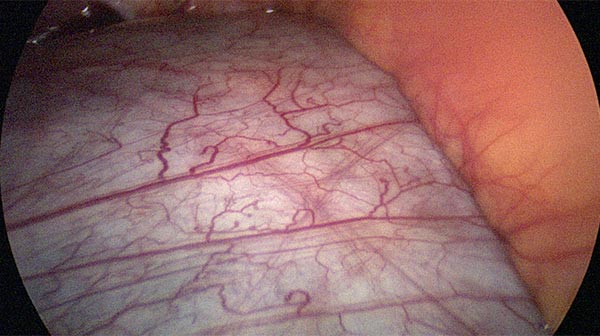

View from the umbilicus to the right upper abdomen with liver and gallbladder. In the mesentery of the small intestine, additional translucent cysts of the lymphatic malformation (LM).

Laparoscopic resection of more than 90% of the cysts. View of the retroperitoneally located cysts of the lymphatic malformation which are visible through the peritoneum.